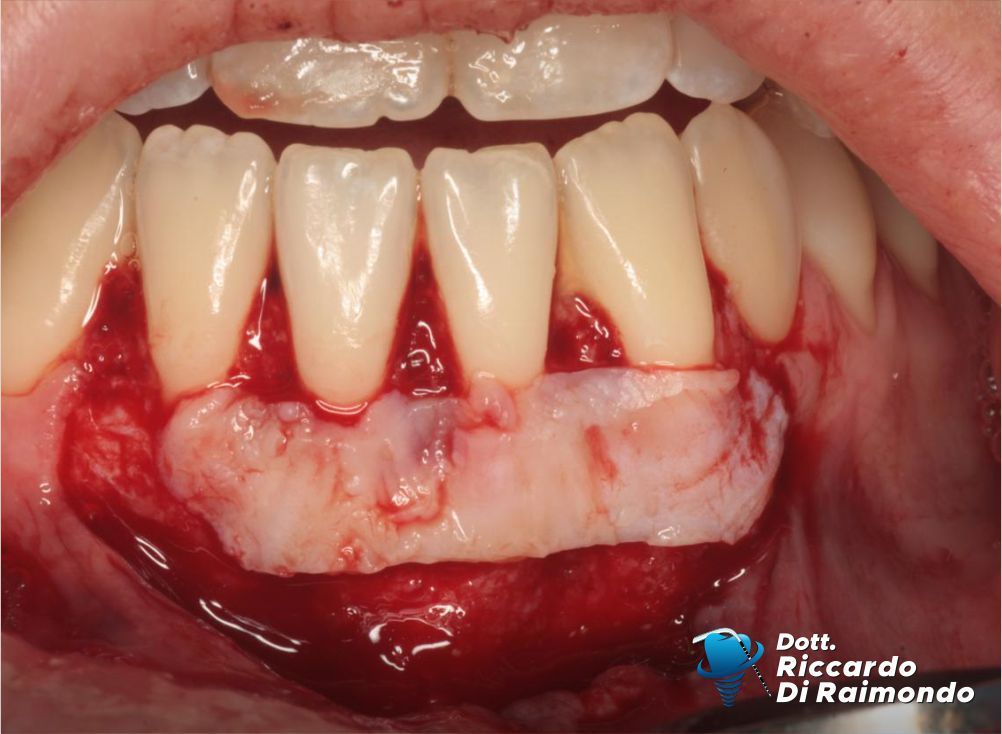

La procedura chirurgica ha previsto il prelievo di un innesto di tessuto connettivo dal palato, successivamente utilizzato per aumentare lo spessore dei tessuti nell’area interessata. La copertura delle recessioni è stata quindi eseguita mediante una tecnica di avanzamento coronale modificato, particolarmente indicata nel trattamento delle recessioni multiple.

Prima del Trattamento

Durante il Trattamento